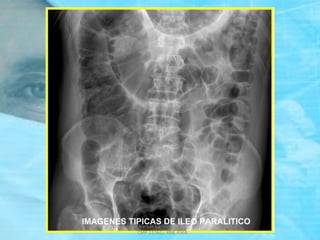

RADIOGRAFIA SIMPLE DE ABDOMEN

DE PIE Y DECUBITO

 Mejor valor diagnóstico.

 Se debe tomar en posición DE PIE

y DECUBITO, incluir diafragma

y pelvis.

 Rx. de PIE: NHA.

 Rx. de DECUBITO:

Gas Intraintestinal

ASAS YEYUNALES:

SIGNO

“PILA DE MONEDAS”

Dr. Eugenio Vargas Carbajal

IMAGEN DE

“COLLAR DE CUENTAS” ó

“SIGNO DEL ROSARIO”

( PRE – OBSTRUCCION )

NIVELES HIDROAEREOS